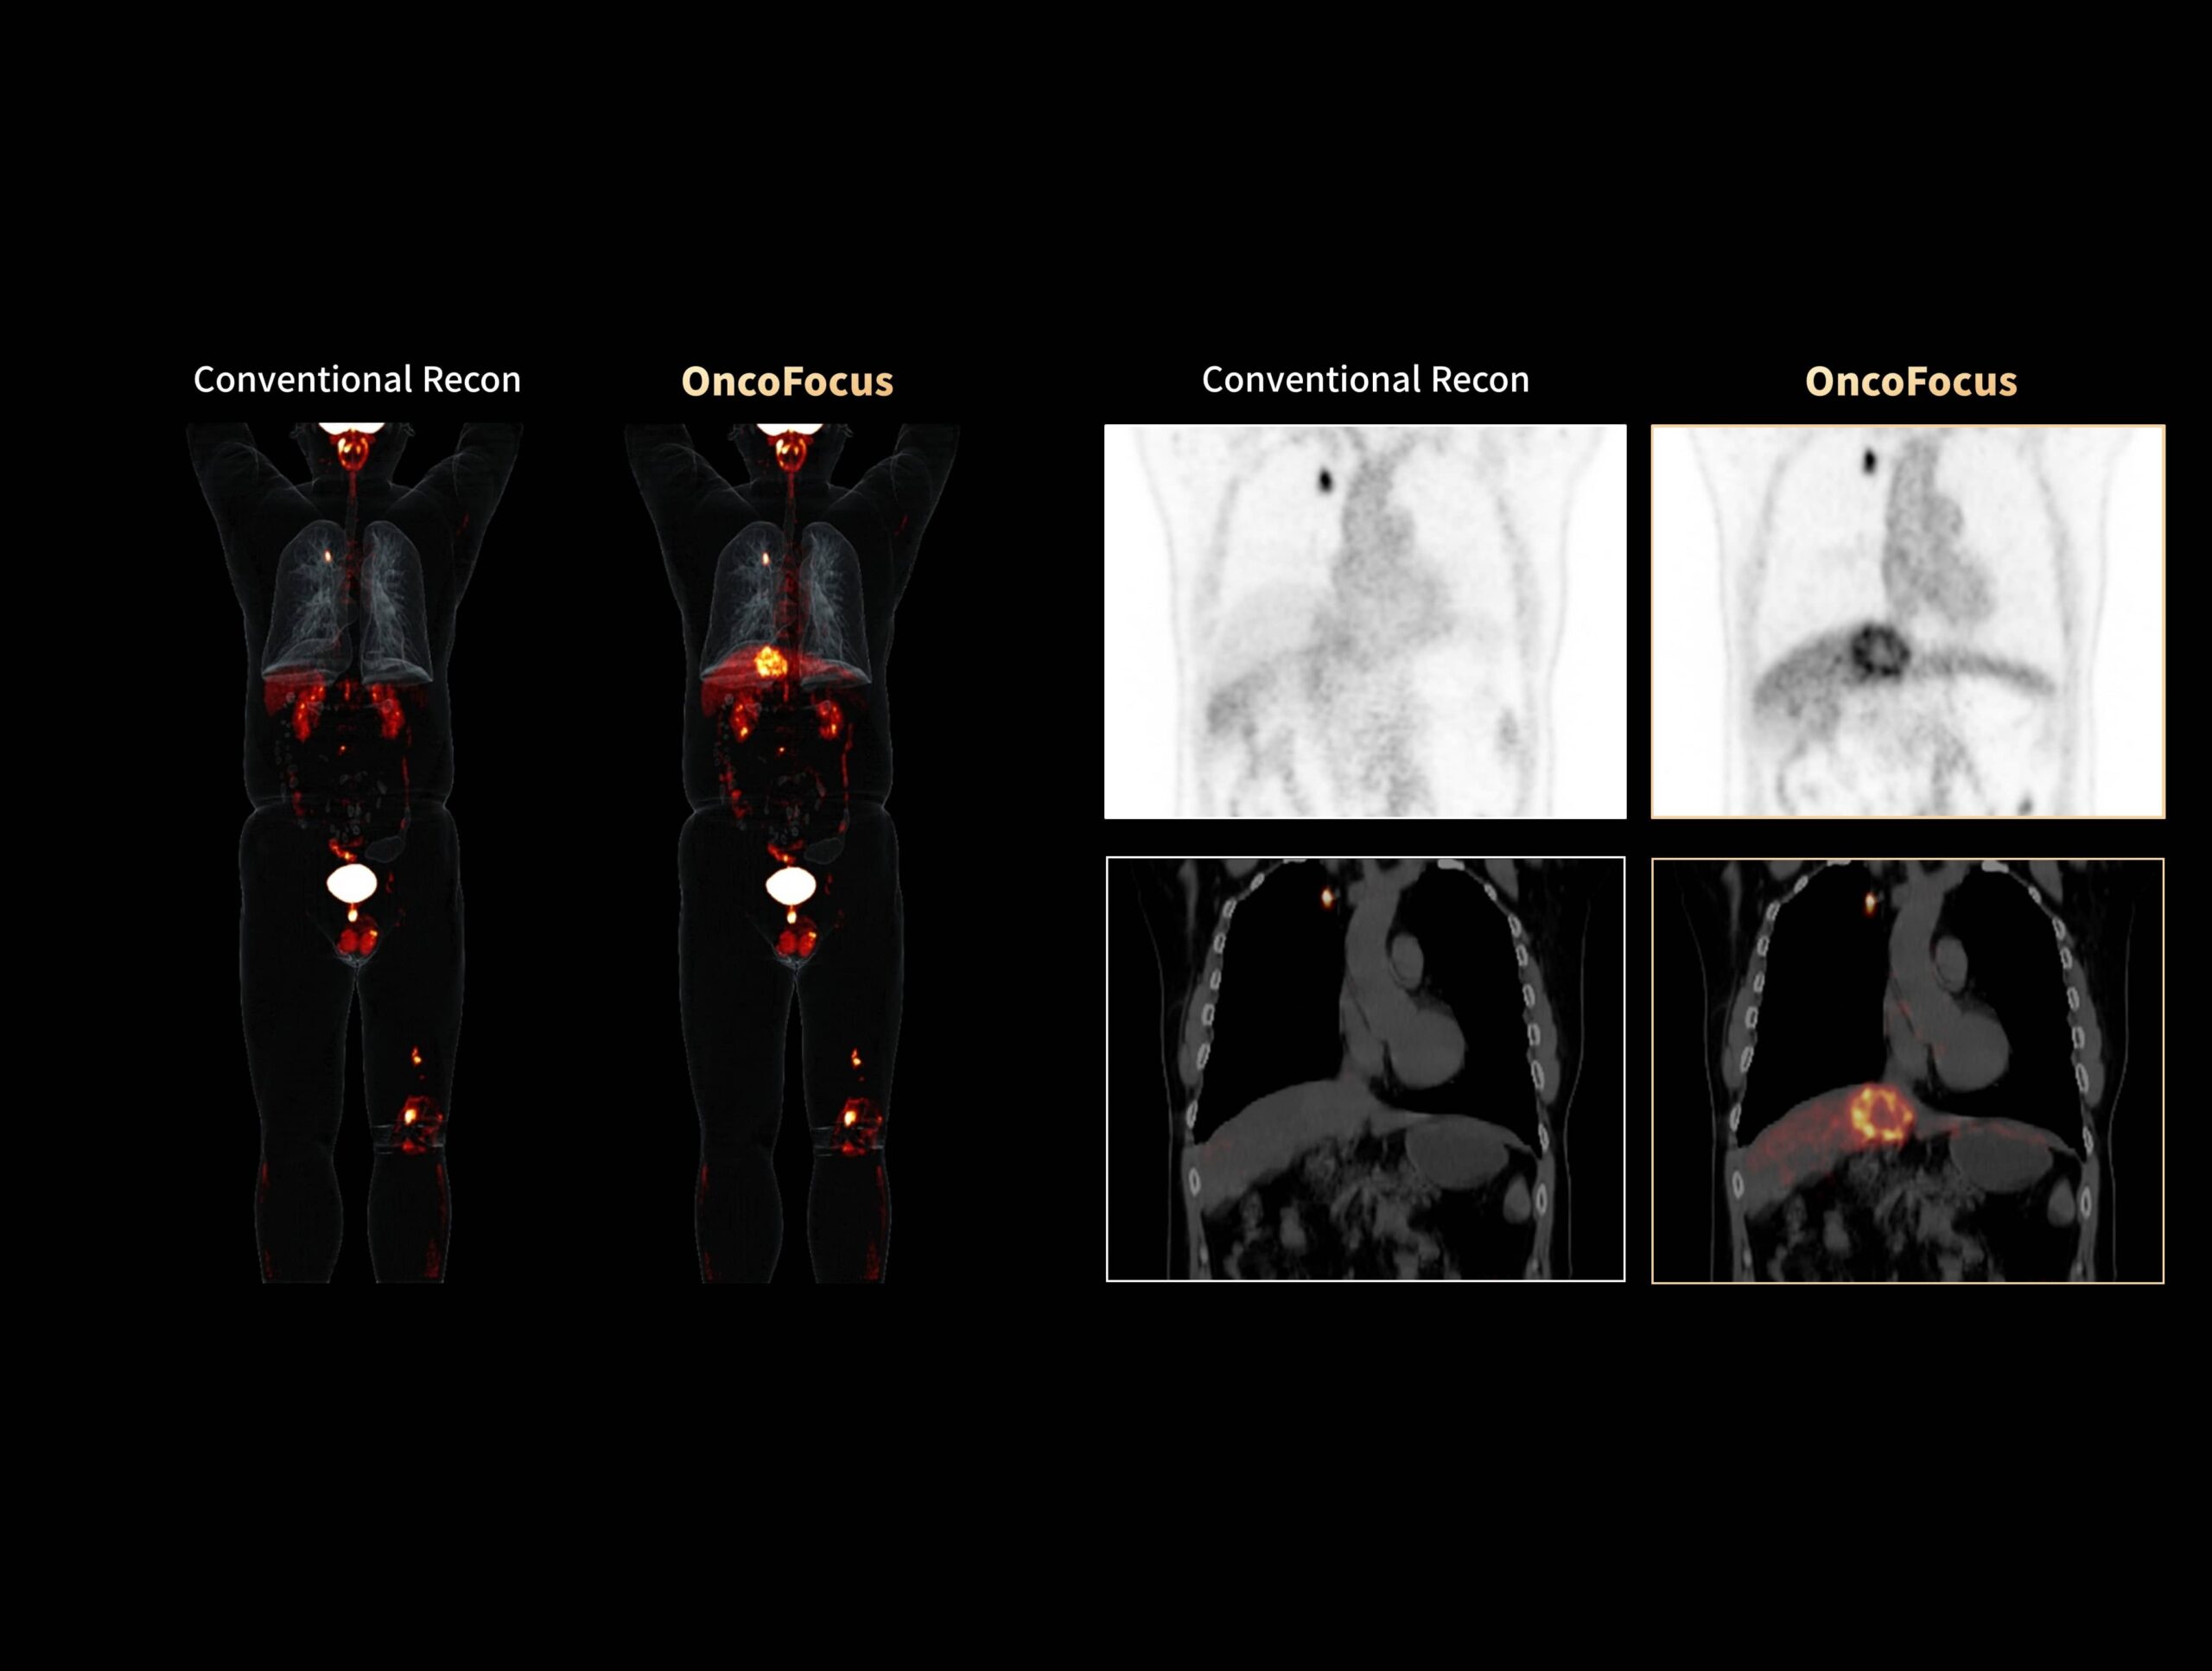

OncoFocus evidențiază clar leziunile hepatice și gastrice

Cancerul pulmonar cu metastaze hepatice greu vizibile poate fi detectat cu OncoFocus